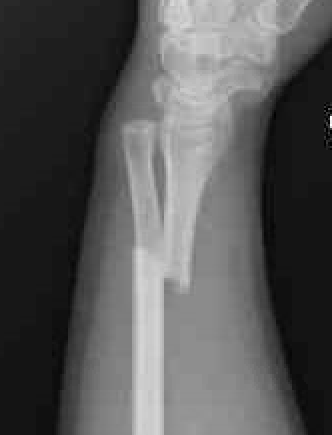

Shortening of radius with disruption of DRUJ on lateral

Concern for disruption of DRUJ on lateral